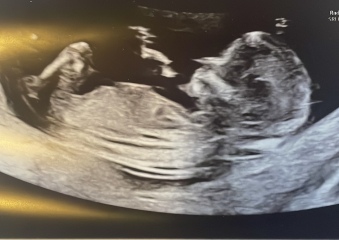

Nub? Is there no nub? Anyone got any guesses

Hello! I am expecting a 3rd (yikes!) and none of mine of my husbands family have girls so there is a lot of pressure. We are going to find out in a few weeks but just wanted to see what people thought? I’m happy with either but feeling the pressure to produce a girl 😬🫣. I have A LOT of photos. Asked for 2 but got 5 so I’ll post them all 😂

lemongirl1985 · 27/03/2025 22:53

Girl 🧒

MilsCookie · 02/04/2025 21:07

I think it’s quite hard to see but I think girl! X

Jessmumofboys · 20/04/2025 21:23

You were both right! I’ve had an early scan and she is indeed a girl! Thank you both for your help 😍